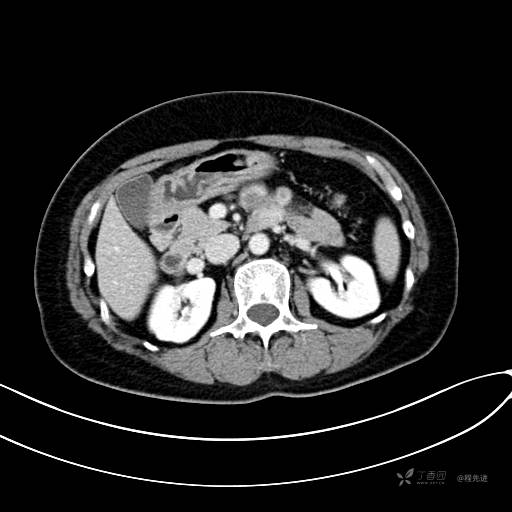

CT增强门脉期